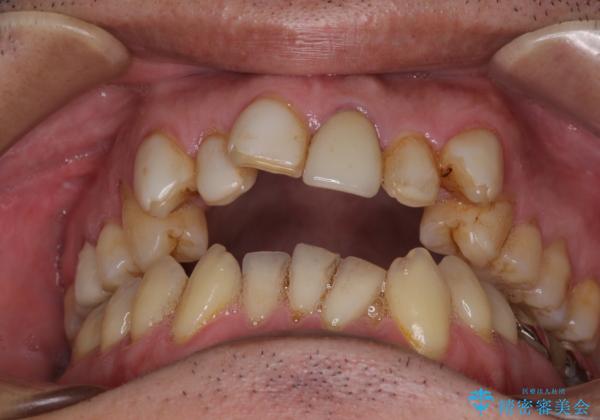

- 長年気になっていた口元を改善したいとのことで来院された患者様です。

外科手術を併用した矯正治療を検討するほどに隙間の空いた開咬と、顕著な叢生が認められました。

外科処置は希望されなかったので、開咬の改善は限界があると事前にお話ししていたため、上下前歯が完全に接触する前に、もう十分改善したとのことで治療を終了しました。

インビザラインを毎日22時間しっかりと装着してくださったので、我々も驚愕するほどの治療成果が達成されました。